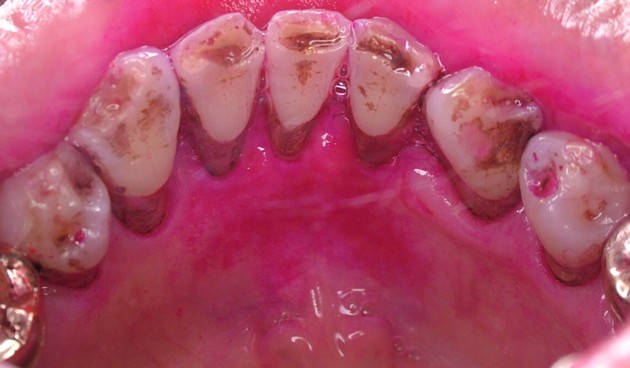

■■■ 色素沈着 ■■■

飲食物や嗜好品(コーヒーやお茶など)、体液中に含まれるメラニン色素などが歯面上に沈着したものです。直接的には為害作用はありませんが、審美性の問題や、あまり厚く沈着すると歯垢が付着しやすくなります。歯磨剤の的確な使用や歯科医師や歯科衛生士による歯冠研磨できれいになります。写真は下顎前歯の内側に見られる色素沈着です。